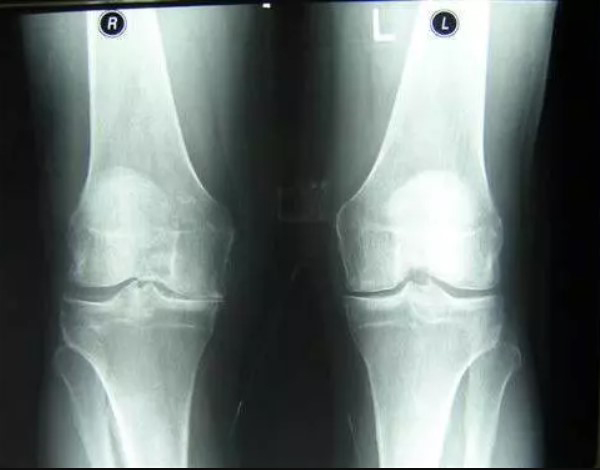

Voici les résultats des personnes qui ont participé aux tests de Marukaya Cream :